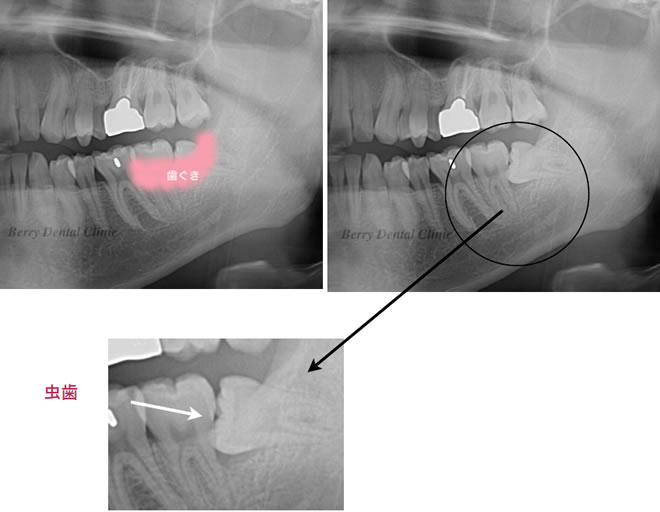

左の実際のお口の中の画像ように親知らずが横になっている為プラークがたまりやすく親知らずの前の歯も虫歯になっています。

舌の2枚の画像はそのレントゲン画像で、左側はピンク色の歯ぐきを入れて加工しています。

右の画像のように歯ぐき画像のピンク色の部分を除去すると矢印の部分の親知らずの前の歯に黒い画像があり、それが虫歯になっている事を示します。

そのまま放置しているかぎり虫歯の歯の治療ができなので、抜歯になります。